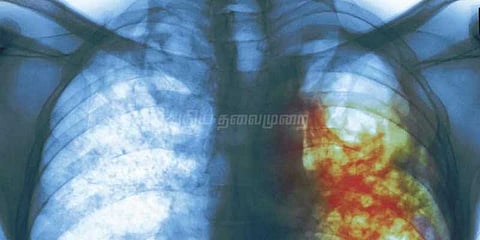

காசநோயாளிகளுக்கு மாதந்தோறும் ரூ.500 வழங்க மத்திய அரசு முடிவு

காசநோயால் பாதிக்கப்பட்ட நோயாளிகளுக்கு மாதந்தோறும் ரூ.500 வழங்க மத்திய அரசு முடிவு செய்துள்ளது.